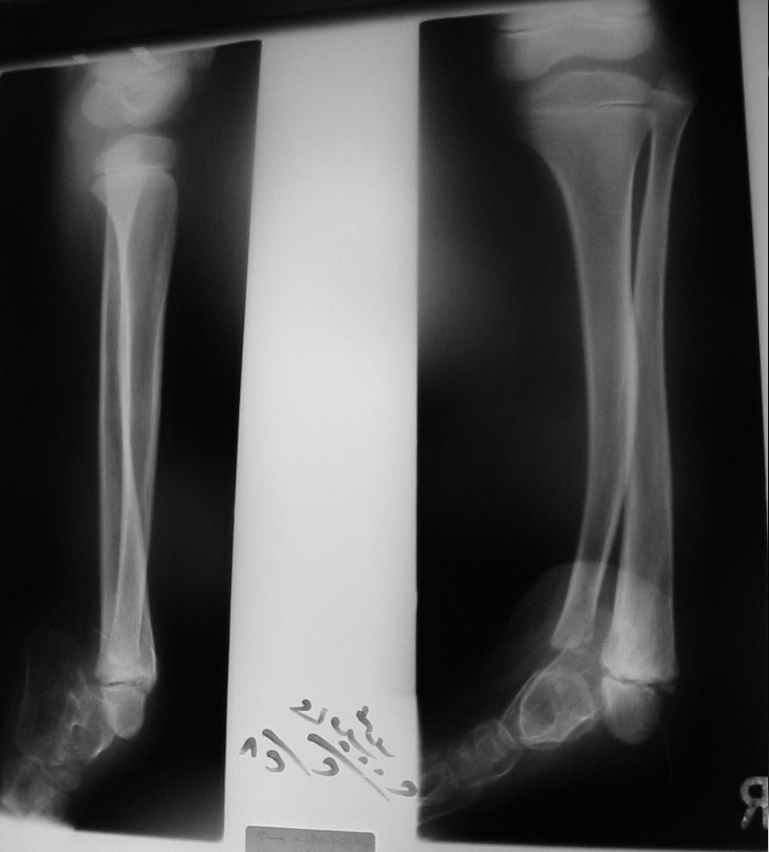

Судя по представленным фото и Рг граммам, у 13 летнего ребенка врождённая гемимелия большеберцовой кости, таранно-пяточный синостоз Из-за отставания в росте большеберцовой кости (остутствует дистальный эпифиз с зоной роста) произошла компенсаторная гиперофия малоберцовой кости, на которую приходится основная нагрузка (спонтанная тибиализация малоберцовой кости). Как результат дисбаланса осевого роста вторично возникла эквино-варусная деформация стопы. Продолжающийся рост ребёнка (до естественного закрытия зон роста) будет приводить к усугублению деформации по приведенным выше причинам.

Поднадкостничную остеотомию большеберцовой кости в средней трети с формированием синостоза с малоберцовой ( активно растущей) костью и второй уровень в области дистального тиб/фиб синдесмоза- достигается баланс роста( средне-медиальный и латеральный отделы) в области измененного голеностопного сустава. Коррекция эквино-варусной деформации стопы в аппарате после чрезкожной сегментарной тенотомии ахилова сухожилия. Дело

кропотливое и длительное.

Как резервный вариант может быть рассмотрена ампутация в верхней трети голени с изготовлением функционального протеза, если родители ребенка не настроены на длительную коррекцию и многоэтапную хирургию, родственники должны понимать, что абсолютного функционального результата даже после этапных операций достичь будет невозможно (аномальный голеностопный сустав, таранно-пяточный синостоз).

В принципе согласен с первым вариантом решения проблемы, правда с оговорками. Думаю к двойной остеотомии стоит отнестись с большой осторожностью, ввиду склонности подобных гипоплазированных гостей к ложняку. Если всё-таки решитесь на одноэтапный оперативный метод, то только под прекрытием удовлетворительных результатов сравнительной денситометрии и изотопного исследования.